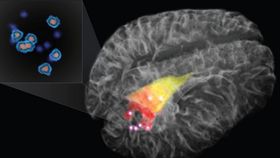

The team tested their probe (pictured to the right) with 17 neurosurgical patients who have advanced gliomas. In addition to dense tumor masses, the device was able to detect individual cancer cells that have invaded the surrounding tissue with 92 percent accuracy.

The team tested their probe (pictured to the right) with 17 neurosurgical patients who have advanced gliomas. In addition to dense tumor masses, the device was able to detect individual cancer cells that have invaded the surrounding tissue with 92 percent accuracy.

In the 3D rendering above, the red and yellow areas indicate cancer that was detected using an MRI. The bright points—cancers detected using Raman spectroscopy—are well beyond what’s detectable using MRI. The Montreal Neurological Institute and Hospital will be launching a clinical trial for patients with newly diagnosed and recurrent glioblastoma.